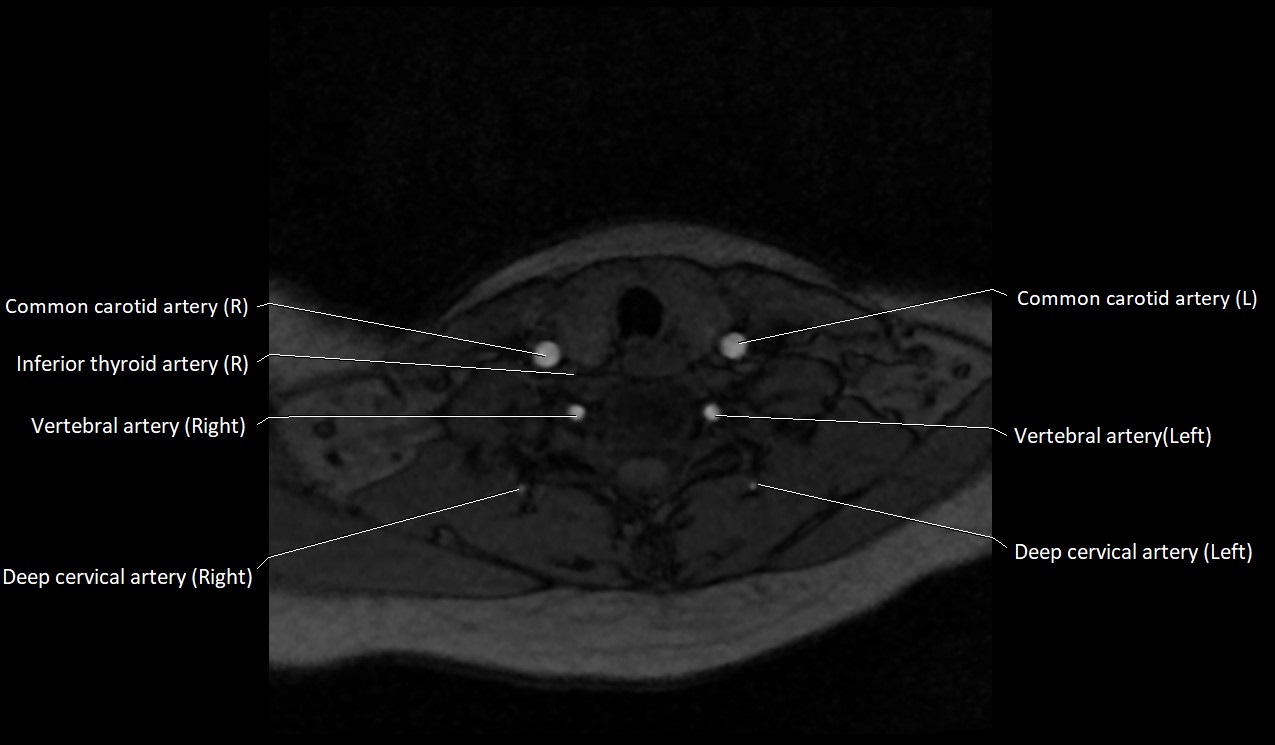

CT image

image